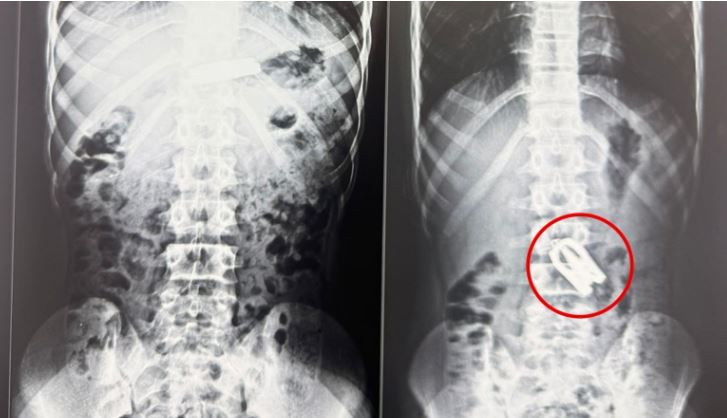

पूर्णपुष्टि, असार ४ । उदयपुरका एक १५ बर्षीय बालकले खेल्ने क्रममा निलेको कैँची नोबेल मेडिकल कलेज टिचिङ हस्पिटलमा अपरेसन गरेर निकालिएको छ । आकस्मिक कक्षमा ल्याईएको बालकको एक्स–रे र सिटी स्क्यानको आधारमा पेटको ठुलो आन्द्राभित्र कैँची अड्किएको पुष्टि भएको थियो ।

घटना अत्यन्तै जटिल र संवेदनशील रहे पनि नोबेल शिक्षण अस्पतालका वरिष्ठ ल्याप्रोस्कोपिक सर्जन डा अमित भट्टराई र उनको सर्जिकल टोलीले ल्याप्रोस्कोपिक प्रविधिको सहायताले सफलतापूर्वक शल्यक्रिया गरी कैँची निकालेका हुन् । डा अमित भट्टराईले बालकको आन्द्रामा कैँची अड्किएको र समयमै ल्याप्रोस्कोपिक सर्जरीमार्फत कैँची निकाल्न सफल भएको बताएका छन् । अहिले बालकको अवस्था सामान्य रहेको उनले बताए । शल्यक्रियापछि बालक दुई दिनमा स्वस्थ भई घर फर्किएका छन् । हेडलाईनमा १५ बालक हुन पुगेकोले १५ बर्षीय बालक भनेर सच्याईएको छ ।